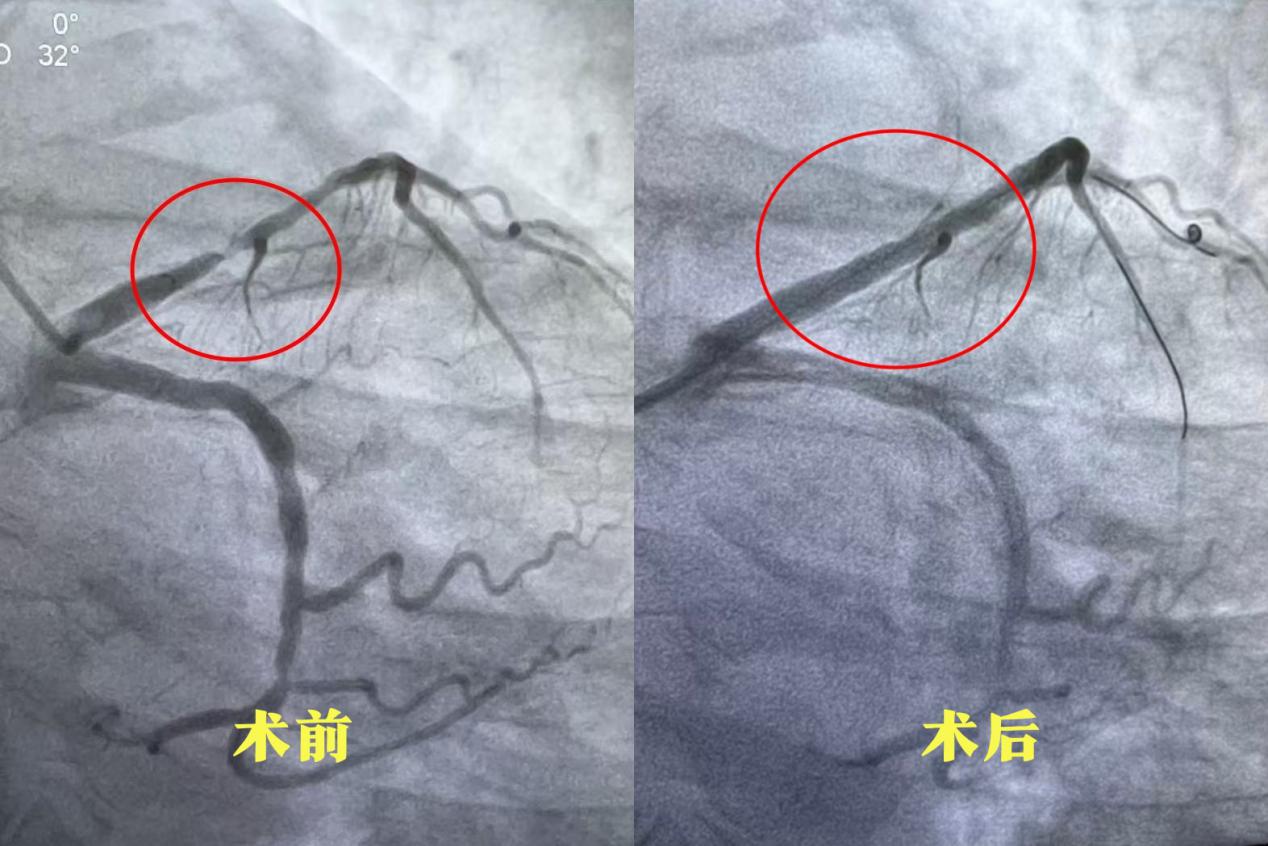

其中,31岁的关先生因恶心、呕吐等消化道症状就诊,经检查确诊为心肌梗死,急诊冠脉造影提示右冠脉闭塞。团队迅速启动绿色通道,及时开通梗死相关血管并植入支架,患者转危为安。